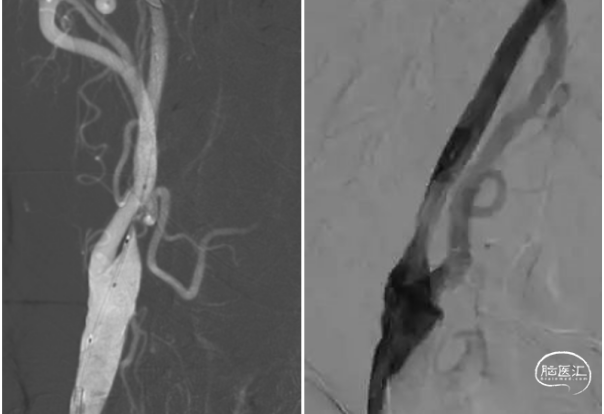

回撤5F中间导管于颈总动脉造影显示颈内动脉起始段重度狭窄。(下图1)

在C1段置入5mm保护伞,用3mm和4mm球囊扩张狭窄部位,但撤出球囊后狭窄略有改善。(下图2)

置入6~8~40mm自膨支架,支架位置良好,残余狭窄约30%。(下图3)

回撤导管与颈总动脉造影支架位置良好,远端大脑中动脉显影良好,分叉部无明确血栓征象。可能经替罗非班推注和血管通畅后逃逸的小血栓溶解了。再通后流动的血液就是最好的溶栓剂。